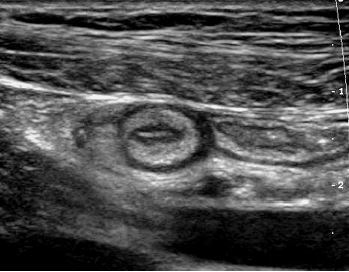

Transverse and longitudinal views of

the mediastinum of the testis